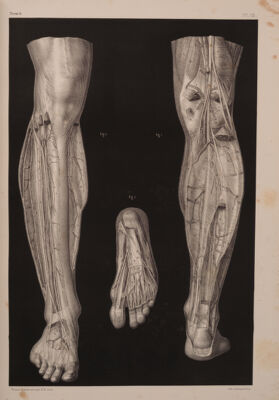

Volume 12

Traité complet de l'anatomie de l'homme comprenant la médecine opératoire ... : avec planches lithographiées ... / par N.H. Jacob.

- Jean-Baptiste Marc Bourgery

- [1831-1854]

Credit: Traité complet de l'anatomie de l'homme comprenant la médecine opératoire ... : avec planches lithographiées ... / par N.H. Jacob. Source: Wellcome Collection.